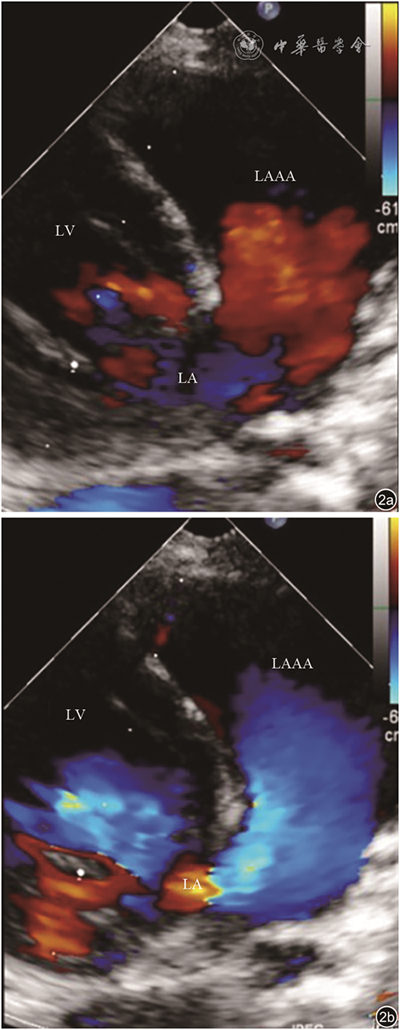

本组病例LAAA内均未见血栓形成,无心包缺损,均为心包内型LAAA。测量LAAA两个径线,长径(32.3±12.9)mm,短径(16.4±6.9)mm。病例1左心室侧壁受压,病例2左心房和左心室重度增大、左心功能减低、二尖瓣中到大量反流,病例4、5合并先天性心脏病,病例6左心房中度增大、二尖瓣中量反流,病例7存在纵隔占位,病例8为肺部肿瘤,病例9存在二尖瓣狭窄伴关闭不全。本组无冠状动脉及肺静脉受压病例。9例患者中1例进行了心脏磁共振成像检查,病例1经心脏磁共振成像证实为LAAA(图5)。

图5 患儿左心耳瘤磁共振心脏亮血序列成像。图a为冠状面显示左心耳瘤(星号所示);图b为横断面显示左心耳瘤(星号所示)